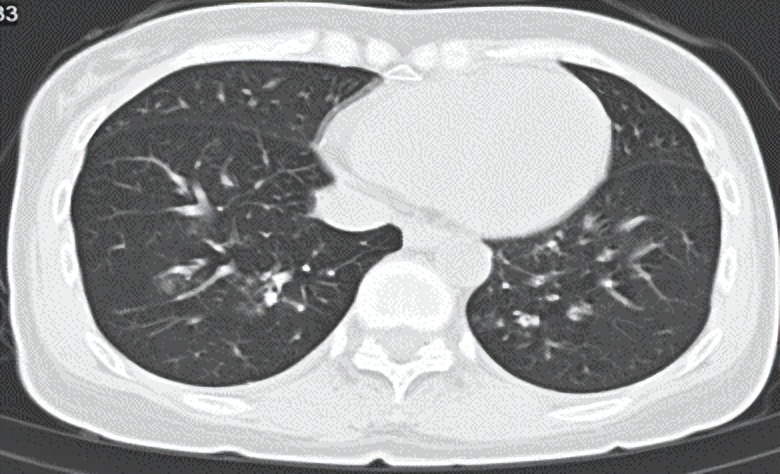

胸部CT显示:右肺多发小斑片状、结节状增高影,考虑感染性病变;

△胸部CT:右肺多发小斑片状、结节状增高影